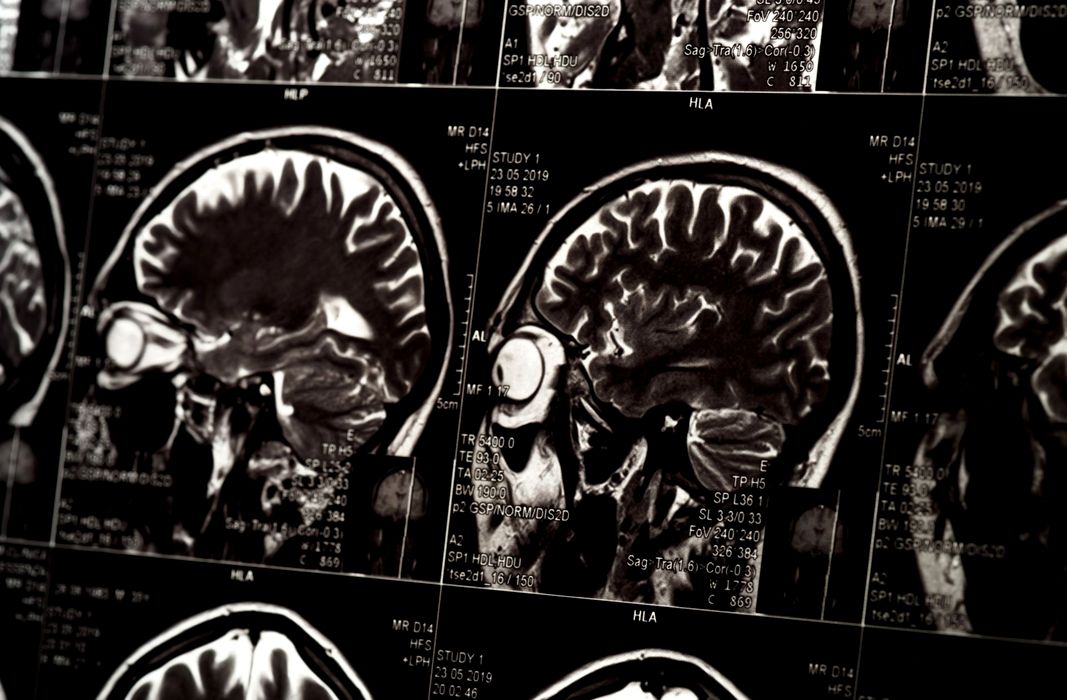

Oamenii de știință ar fi la un pas să rezolve un obstacol major în tratarea creierului

Una dintre cele mai mari provocări în livrarea tratamentelor pentru Alzheimer și alte boli legate de creier este depășirea sistemului robust de apărare pe care creierul îl are pentru a se proteja. Însă, datorită unui […]